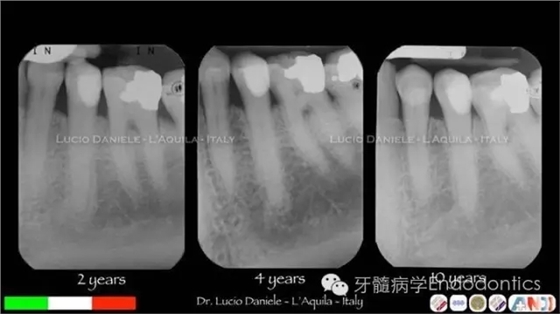

圖5.隨訪2年、4年、10年